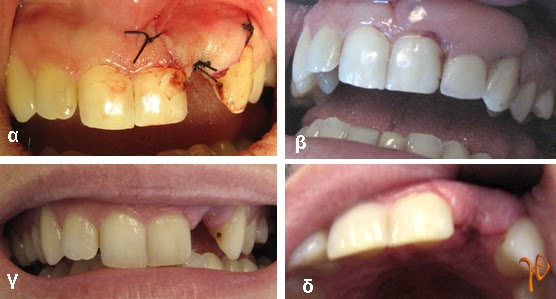

Εικόνα 2.2: (α) συρραφή, (β) προσωρινή κινητή αποκατάσταση ελλείμματος, (γ) και (δ) μετά την αφαίρεση των ραμμάτων.